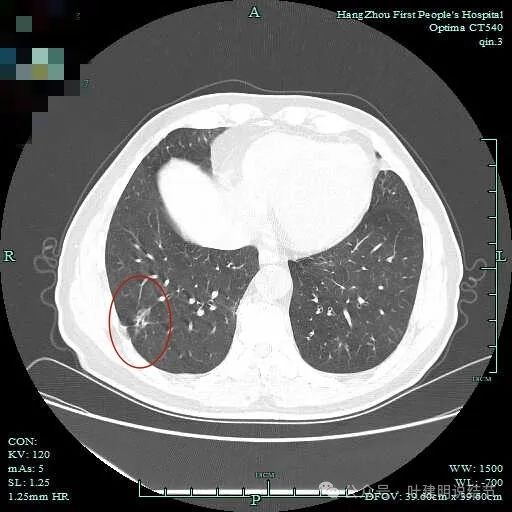

次病灶连续层面观察:

紧贴脊柱处混合密度,趴在脊柱上,这不像结节状。

但有小血管似的,磨玻璃部分界限较清。但此类异常影像在正常人的CT上也挺常见。

密度较高,确实像血管进入。但病灶片状,趴在脊柱上。

此层显得更呈小片状了。

与脊柱间似乎有间隙在,另见微小血管进入这条索状的偏高密度影处。

有细小血管进入,但说不上异常增粗。病灶仍是小片状,条状。

磨玻璃成分密度淡且界欠清,整体就是条索状弯曲的。

上图见细毛刺明显。

病灶实性伴细毛刺,与脊柱间有间隙在。

病仍明显,从上到下,觉得应该是成片的。

表面不平毛刺,实性密度为主。

微小血管有,但无异常增粗。

病灶实性,边缘不光滑。

实性密度,片状,条状。

病灶实性,缺乏膨胀性。

上图呈结节状,表面不平,有少许磨玻璃成分。

结节状,密度高,边缘欠光滑。

与脊柱之间有间隙,表面有细毛刺。

表面不平,似有细支气管截断征。

边缘不平毛糙。

像慢性炎似的。

瘤肺边界欠清。

边缘区淡磨玻璃密度。